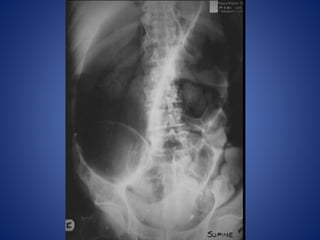

Large Bowel Obstruction

DIAGNOSIS ?

Hernia